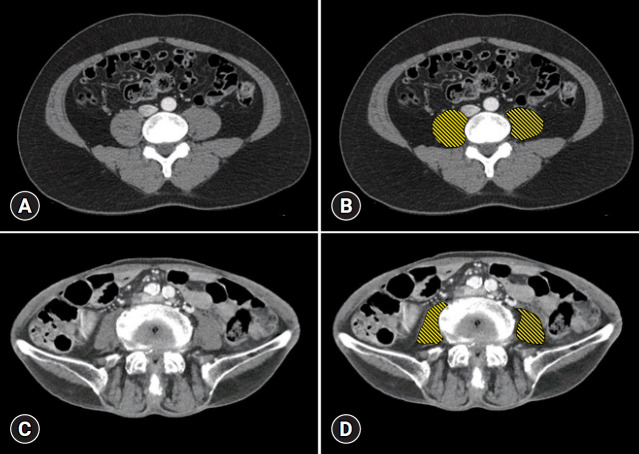

Methods: We retrospectively analyzed 2,050 patients who underwent esophagogastroduodenoscopy for suspected gastrointestinal bleeding between January 2014 and December 2021. Patients who underwent computed tomography scans were included for sarcopenia evaluation based on the psoas muscle index, defined as the total psoas area normalized by the square of the height of the patient. Sarcopenia was defined using specific cutoffs: ≤7.3 cm2/m2 and ≤5.1 cm2/m2 for men and women, respectively. The primary outcome measured was the 30-day mortality rate.